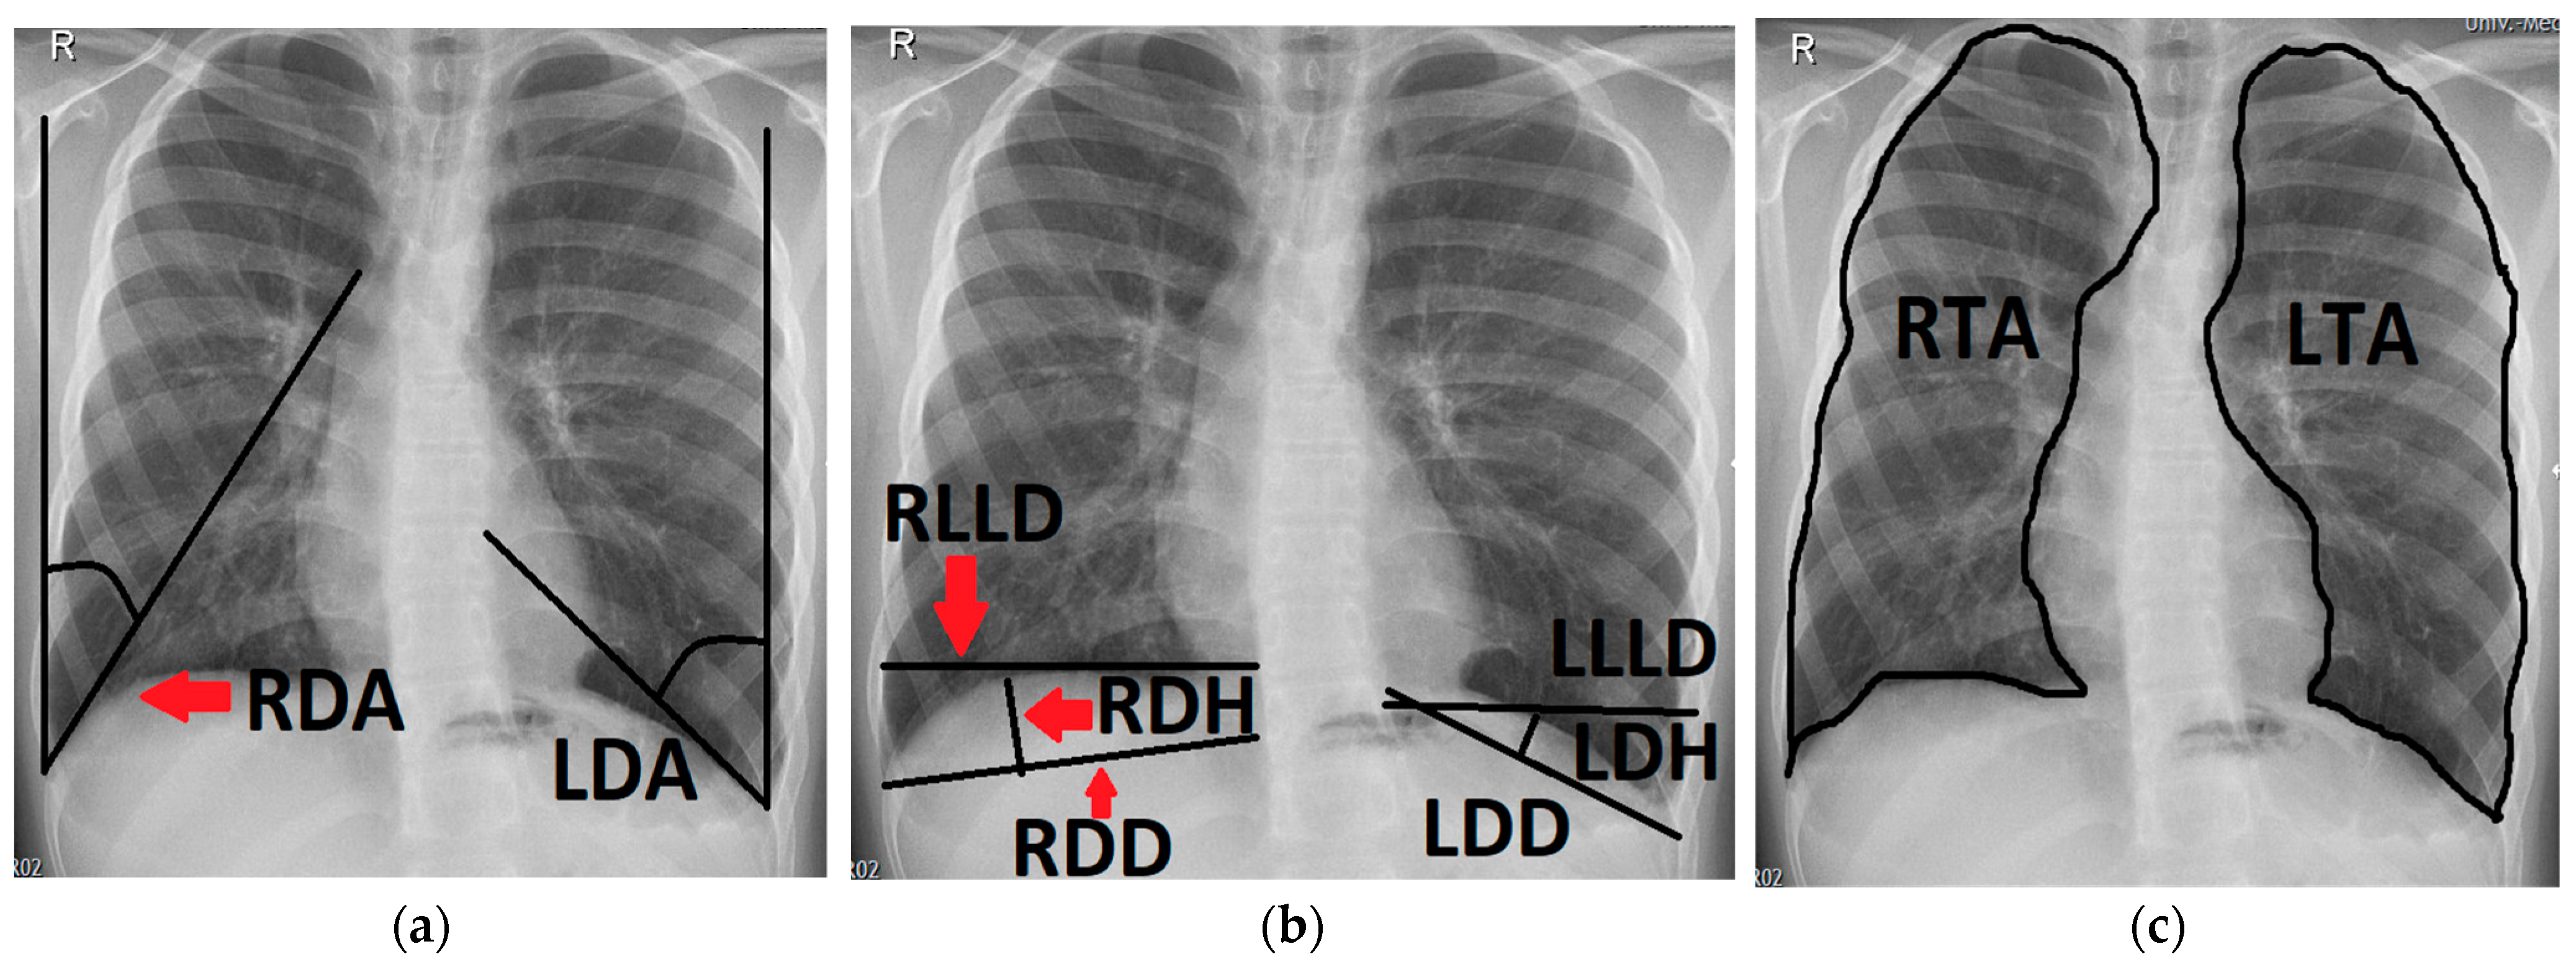

- The left and right diaphragmatic angle (LDA, RDA), which were defined by the angle between the lateral chest wall and the tangent to the convex side of the ipsilateral diaphragm coming from the costodiaphragmatic recessus.

- The left and right diaphragmatic diameter (LDD, RDD), measuring from the costodiaphragmatic recessus to the medial limit of the diaphragm.

- The left and right diaphragmatic height (LDH, RDH), measured as the perpendicular line from the diaphragmatic diameter to the apex of the diaphragm.

- The left and right lower lung diameter (LLLD, RLLD), measuring the width of the lung from its limit at the lateral chest wall to its medial limit at the level of the apex of the diaphragm.

- The left and right thoracic area (LTA, RTA) were defined by delineating the outer border of the lung tissue, excluding the mediastinum and the cardiac shadow.

- The left and right diaphragmatic curvature index (LDCI, RDCI) were calculated via the quotient of the diaphragmatic diameter and the diaphragmatic height (e.g., LDD/LDH = LDCI). A large LDCI therefore indicates a flat diaphragm with only a small curvature.